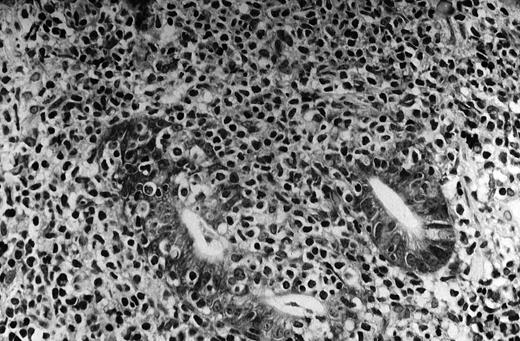

The pivotal feature of low-grade MALT lymphoma is the presence of a variable number of lymphoepithelial lesions that can be defined as unequivocal invasion and partial destruction of gastric glands or crypts by aggregates of tumor cells (Figure1). Lymphoepithelial lesions are of striking relevance for the diagnosis of low-grade gastric MALT lymphoma; however, they can sometimes be seen in the context of florid chronic gastritis and can also be present in other sites of both native and acquired MALT.88 89

The neoplastic lymphocytes infiltrate some residual gastric glands, giving rise to lymphoepithelial lesions (Giemsa staining, × 512, courtesy of Prof Stefano Pileri, University of Bologna, Italy).

The tumor cells are usually small- to medium-sized lymphocytes with moderately abundant cytoplasm and irregularly shaped nuclei resembling those of follicular center cells, or centrocytes, and have been designated centrocyte-like (CCL) cells.1,88 However, although resemblance to centrocytes is the general rule, the morphologic pattern of the neoplastic cells can cover quite a large spectrum. Some are similar to the so-called monocytoid cells (abundant pale cytoplasm and well-defined cell borders), and some are similar to small lymphocytes, sometimes with lymphoplasmacytic features. Any of these cytologic aspects can predominate, or they can coexist to various degrees in the same tumor. Scattered transformed blasts (large cells) can also be found. Some degree of plasma cell differentiation is often present; the plasma cells are sometimes so conspicuous as to suggest a diagnosis of extramedullary plasmacytoma.88 Plasma cells often present varying degrees of atypia, Dutcher bodies, or other intracellular inclusions.1,88,89 The lymphoma cells diffusely infiltrate the lamina propria and grow around reactive follicles. The preexisting germinal centers are selectively overrun, and sometimes extensively replaced, by the neoplastic cells, which often undergo striking plasma cell differentiation after invasion of the follicles. Less commonly, the complex interaction between the CCL cells within the follicles may undergo prominent blast transformation. The complex interaction between the CCL cells and the reactive B-cell follicles is known as follicular colonization.90